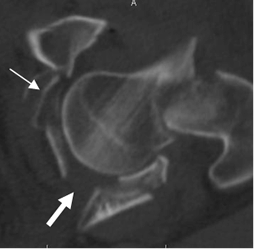

Fig 58. Fractura de acetábulo. Igual paciente anterior.

TAC axial. Fractura del reborde acetabular anterior izquierdo, no sospechada con la Rx simple.

En el lado derecho se aprecian las fracturas ya descritas.